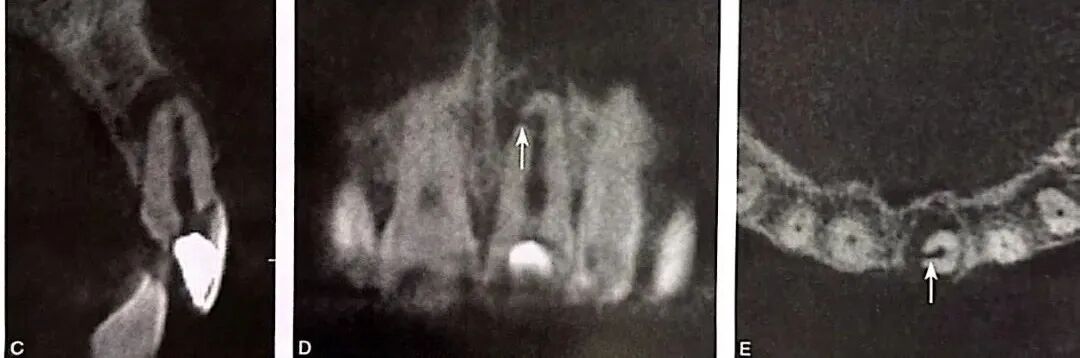

导致根旁牙槽骨破坏的可能病因有根裂、侧支根管、根折、根旁囊肿、牙骨质撕裂等。当根管侧支位于牙根中段时,感染破坏根周牙槽骨,可形成类似根裂的影像学特点,如图3所示,A为口内像颊侧面观,示左下颌第一磨牙近中近龈缘处牙龈窦道(箭头);B为根尖片示根管充填良好,近中根根尖以及根周大范围透射影,波及根分叉区;C为CBCT矢状位;D为CBCT冠状位;E为CBCT水平位,近中根根尖、根周以及根分叉区骨质破坏;F为左下颌第一牙行显微根尖外科手术,切开翻瓣牵拉 ;G为根尖周刮治和根尖切除;H为探查,近中根未见根裂线,近中面中段见根管侧支(箭头);I为主根管和根管侧支逆行预备和充填;J为术后根尖片,可见根管侧支(箭头);K为术后2个月随访根尖片;L为术后4个月随访根尖片;M为术后7个月随访根尖片;N为术后24个月随访根尖片,根周和根尖周完全愈合。